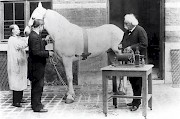

Nach eigenen Aussagen basierte sein späterer Selbstversuch auf den Arbeiten von Claude Bernard, Auguste Chauveau and Étienne-Jules Marey an Haustieren, vor allem Hunden und Pferden.Bernard hatte in dem Lehrbuch Leçons de Physiologie Operatoire einen Holzschnitt veröffentlicht. Er zeigte die Katheterisierung eines auf dem Rücken liegenden Hundes, dem ein Schlauch durch eine geöffnete Halsvene in das Herz geführt worden war, so dass sich der Druck im Herzinneren messen ließ. Forßmann übertrug diese Untersuchungsmethode auf den Menschen, wobei er statt des Halses den besser zugänglichen Arm als Zugang wählte. Er untersuchte die Katheterisierungsmöglichkeit an Leichen und stellte durch eine Autopsie fest, dass er mit einem Schlauch vom Arm bis in das Herz vordringen konnte.

Herzkatheteruntersuchung 1929